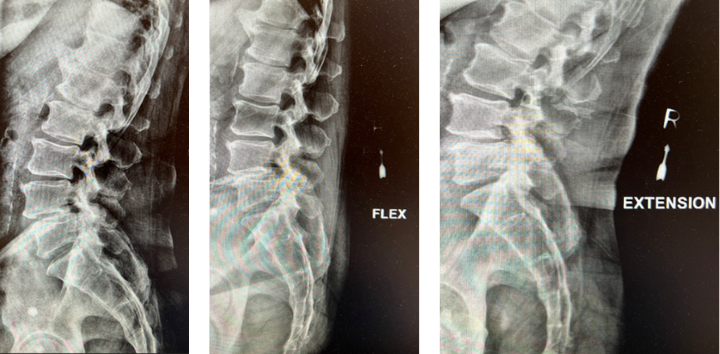

Back:

Revision Surgery Treats Intractable Neck Pain & Cervical Deformity

Author: Benjamin R. Cohen M.D., F.A.A.N.S., F.A.C.S., Read More!